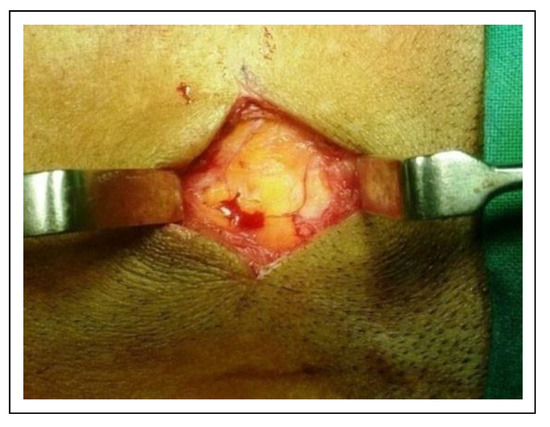

![]() |